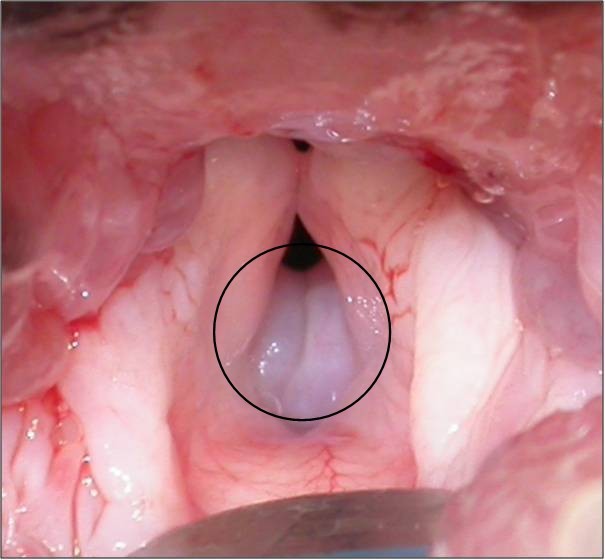

At the beginning of an upper airway examination you notice small pear-shaped masses just in front of the vocal folds. What are these?

Everted laryngeal saccules